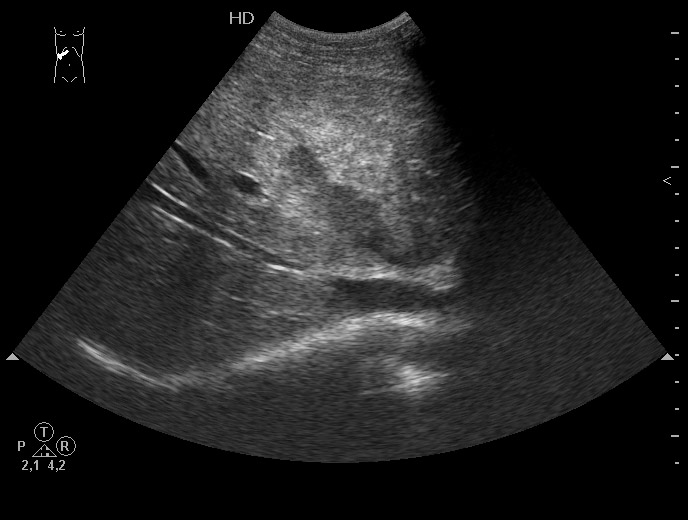

Выставляю картинку, по которой можно установить диагноз практически без дополнительных данных.

Все верно, разрыв печени плюс жидкость в боковом синусе плевральной полости.

Ультразвуковая семиотика разрыва довольно типична. Разместить эту сонограмму решил после того, как увидел протокол из одной авторитетной клиники, где гемангиома была трактована как разрыв печени и внутрипеченочная гематома.

Добавлю еще пару случаев